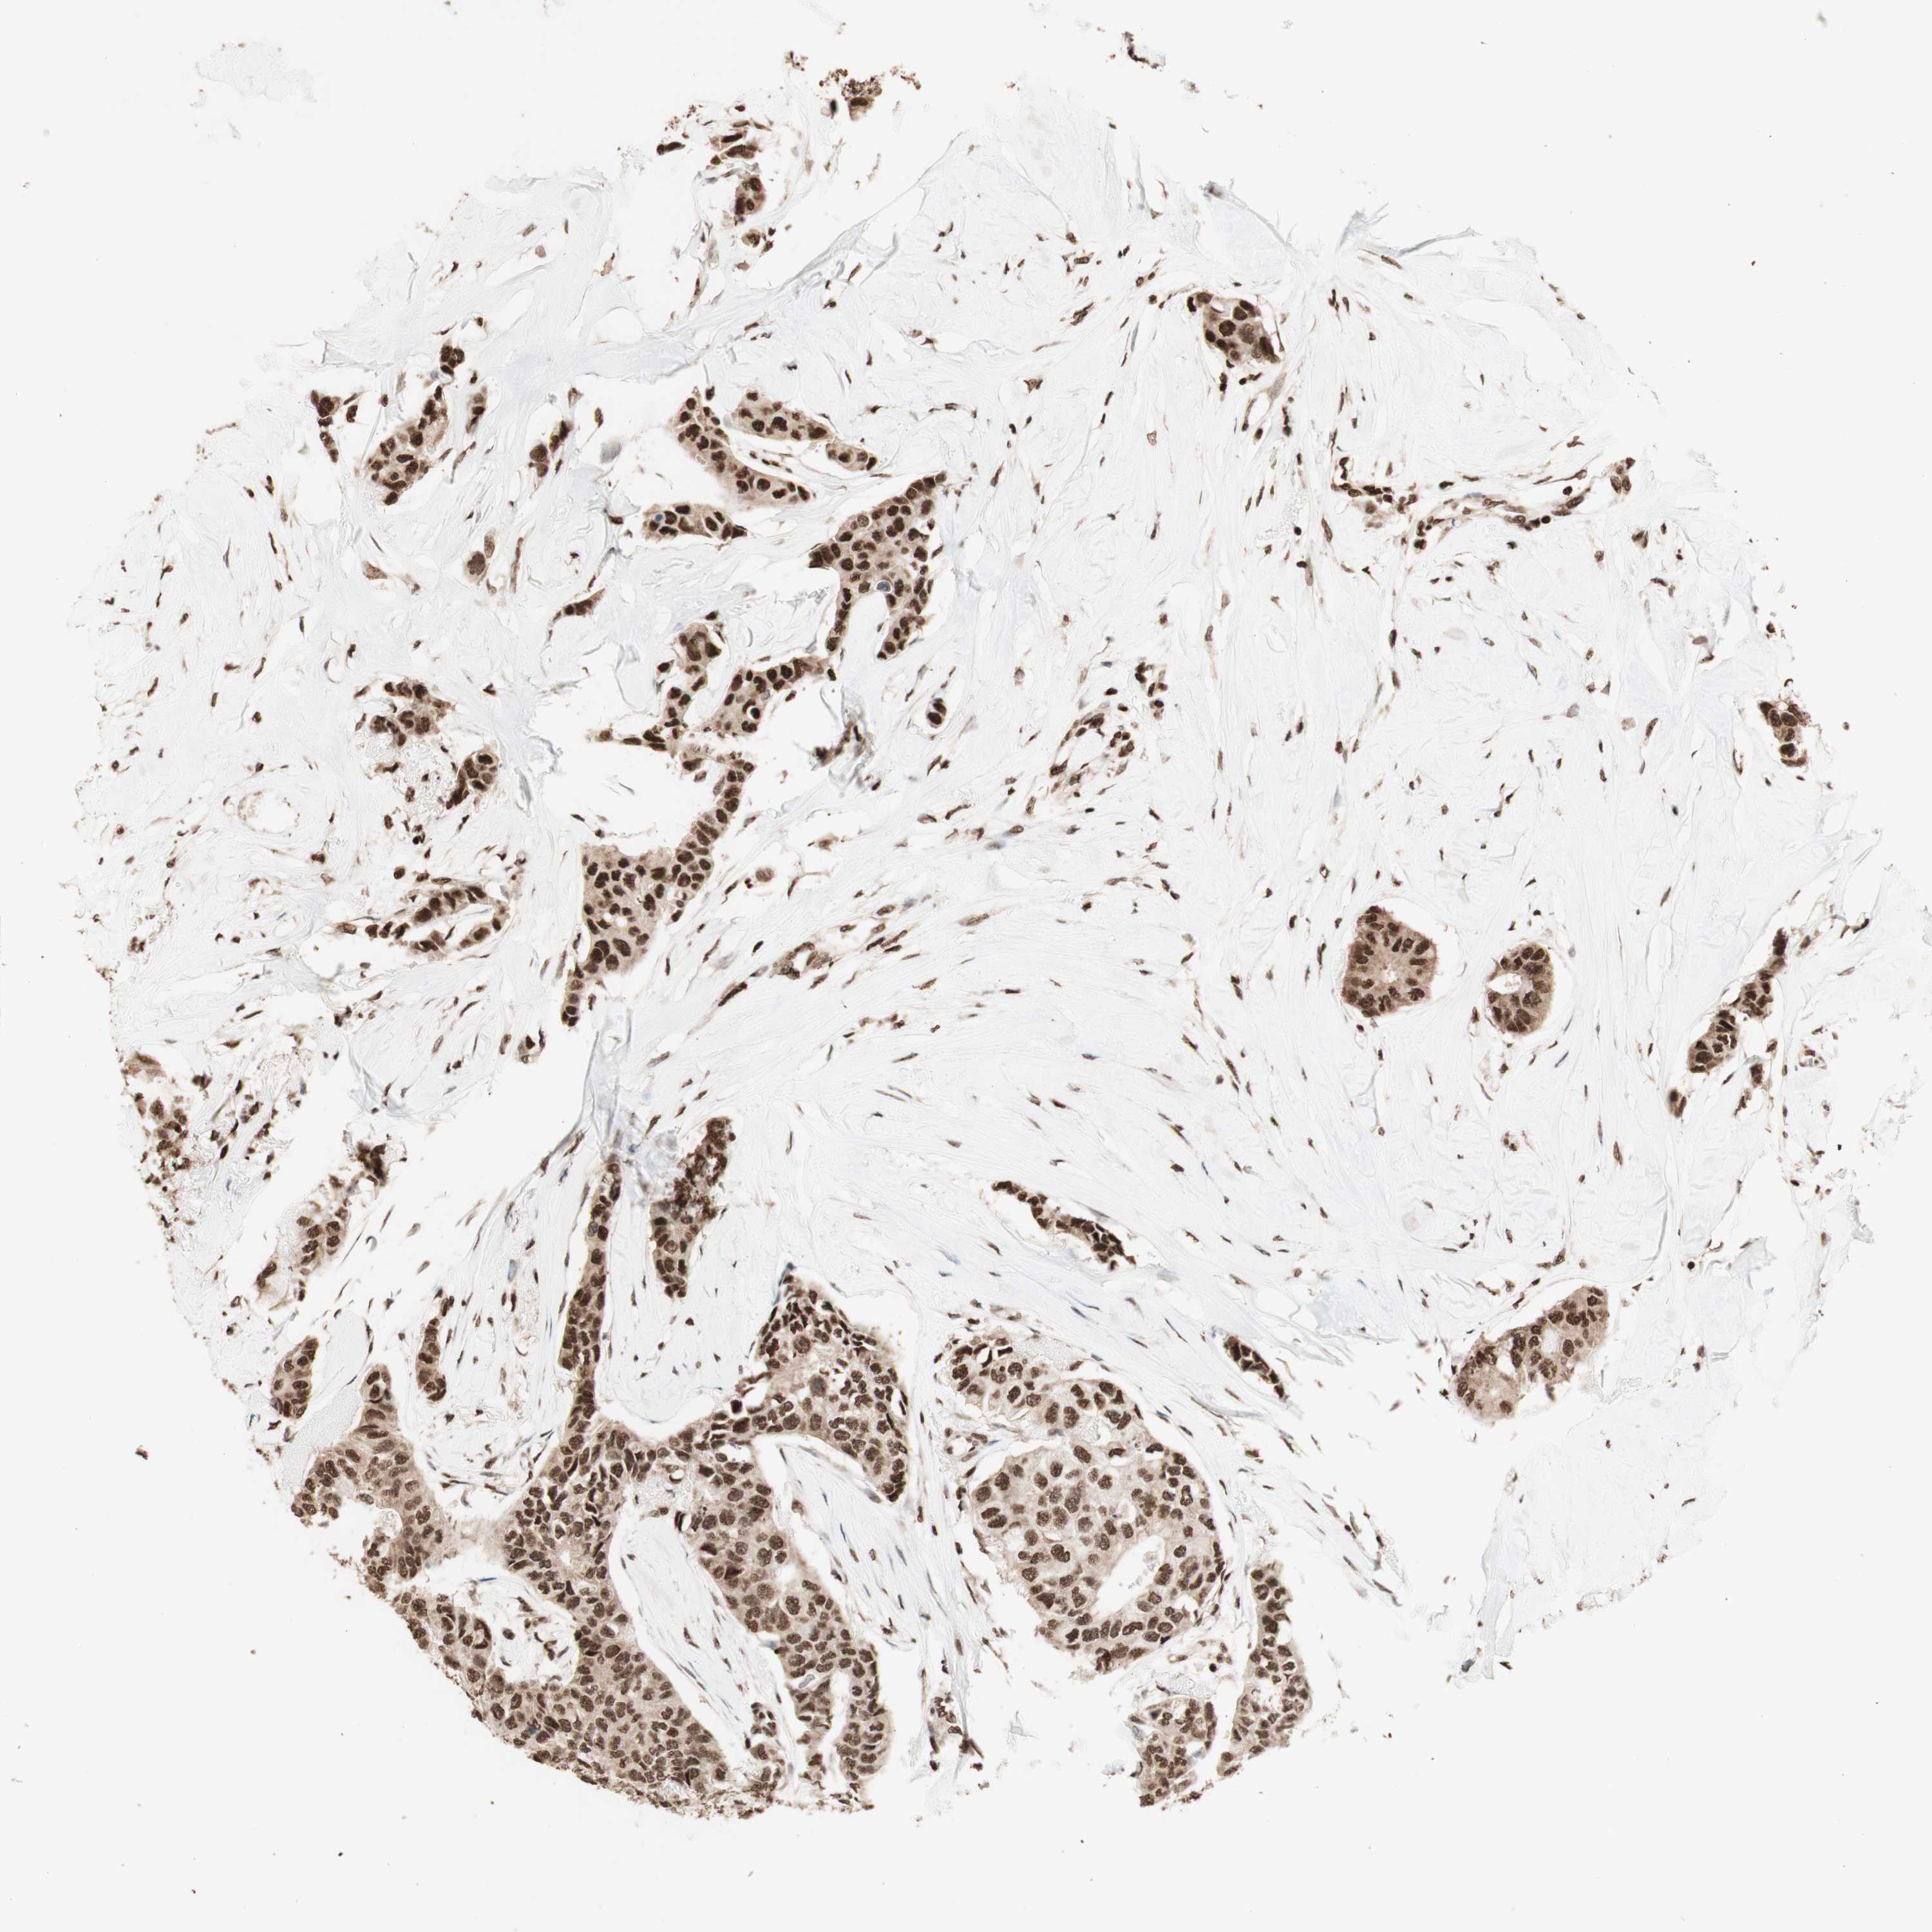

BRCA TCGA BRCA VALIDATION PROTEIN EXPRESSION